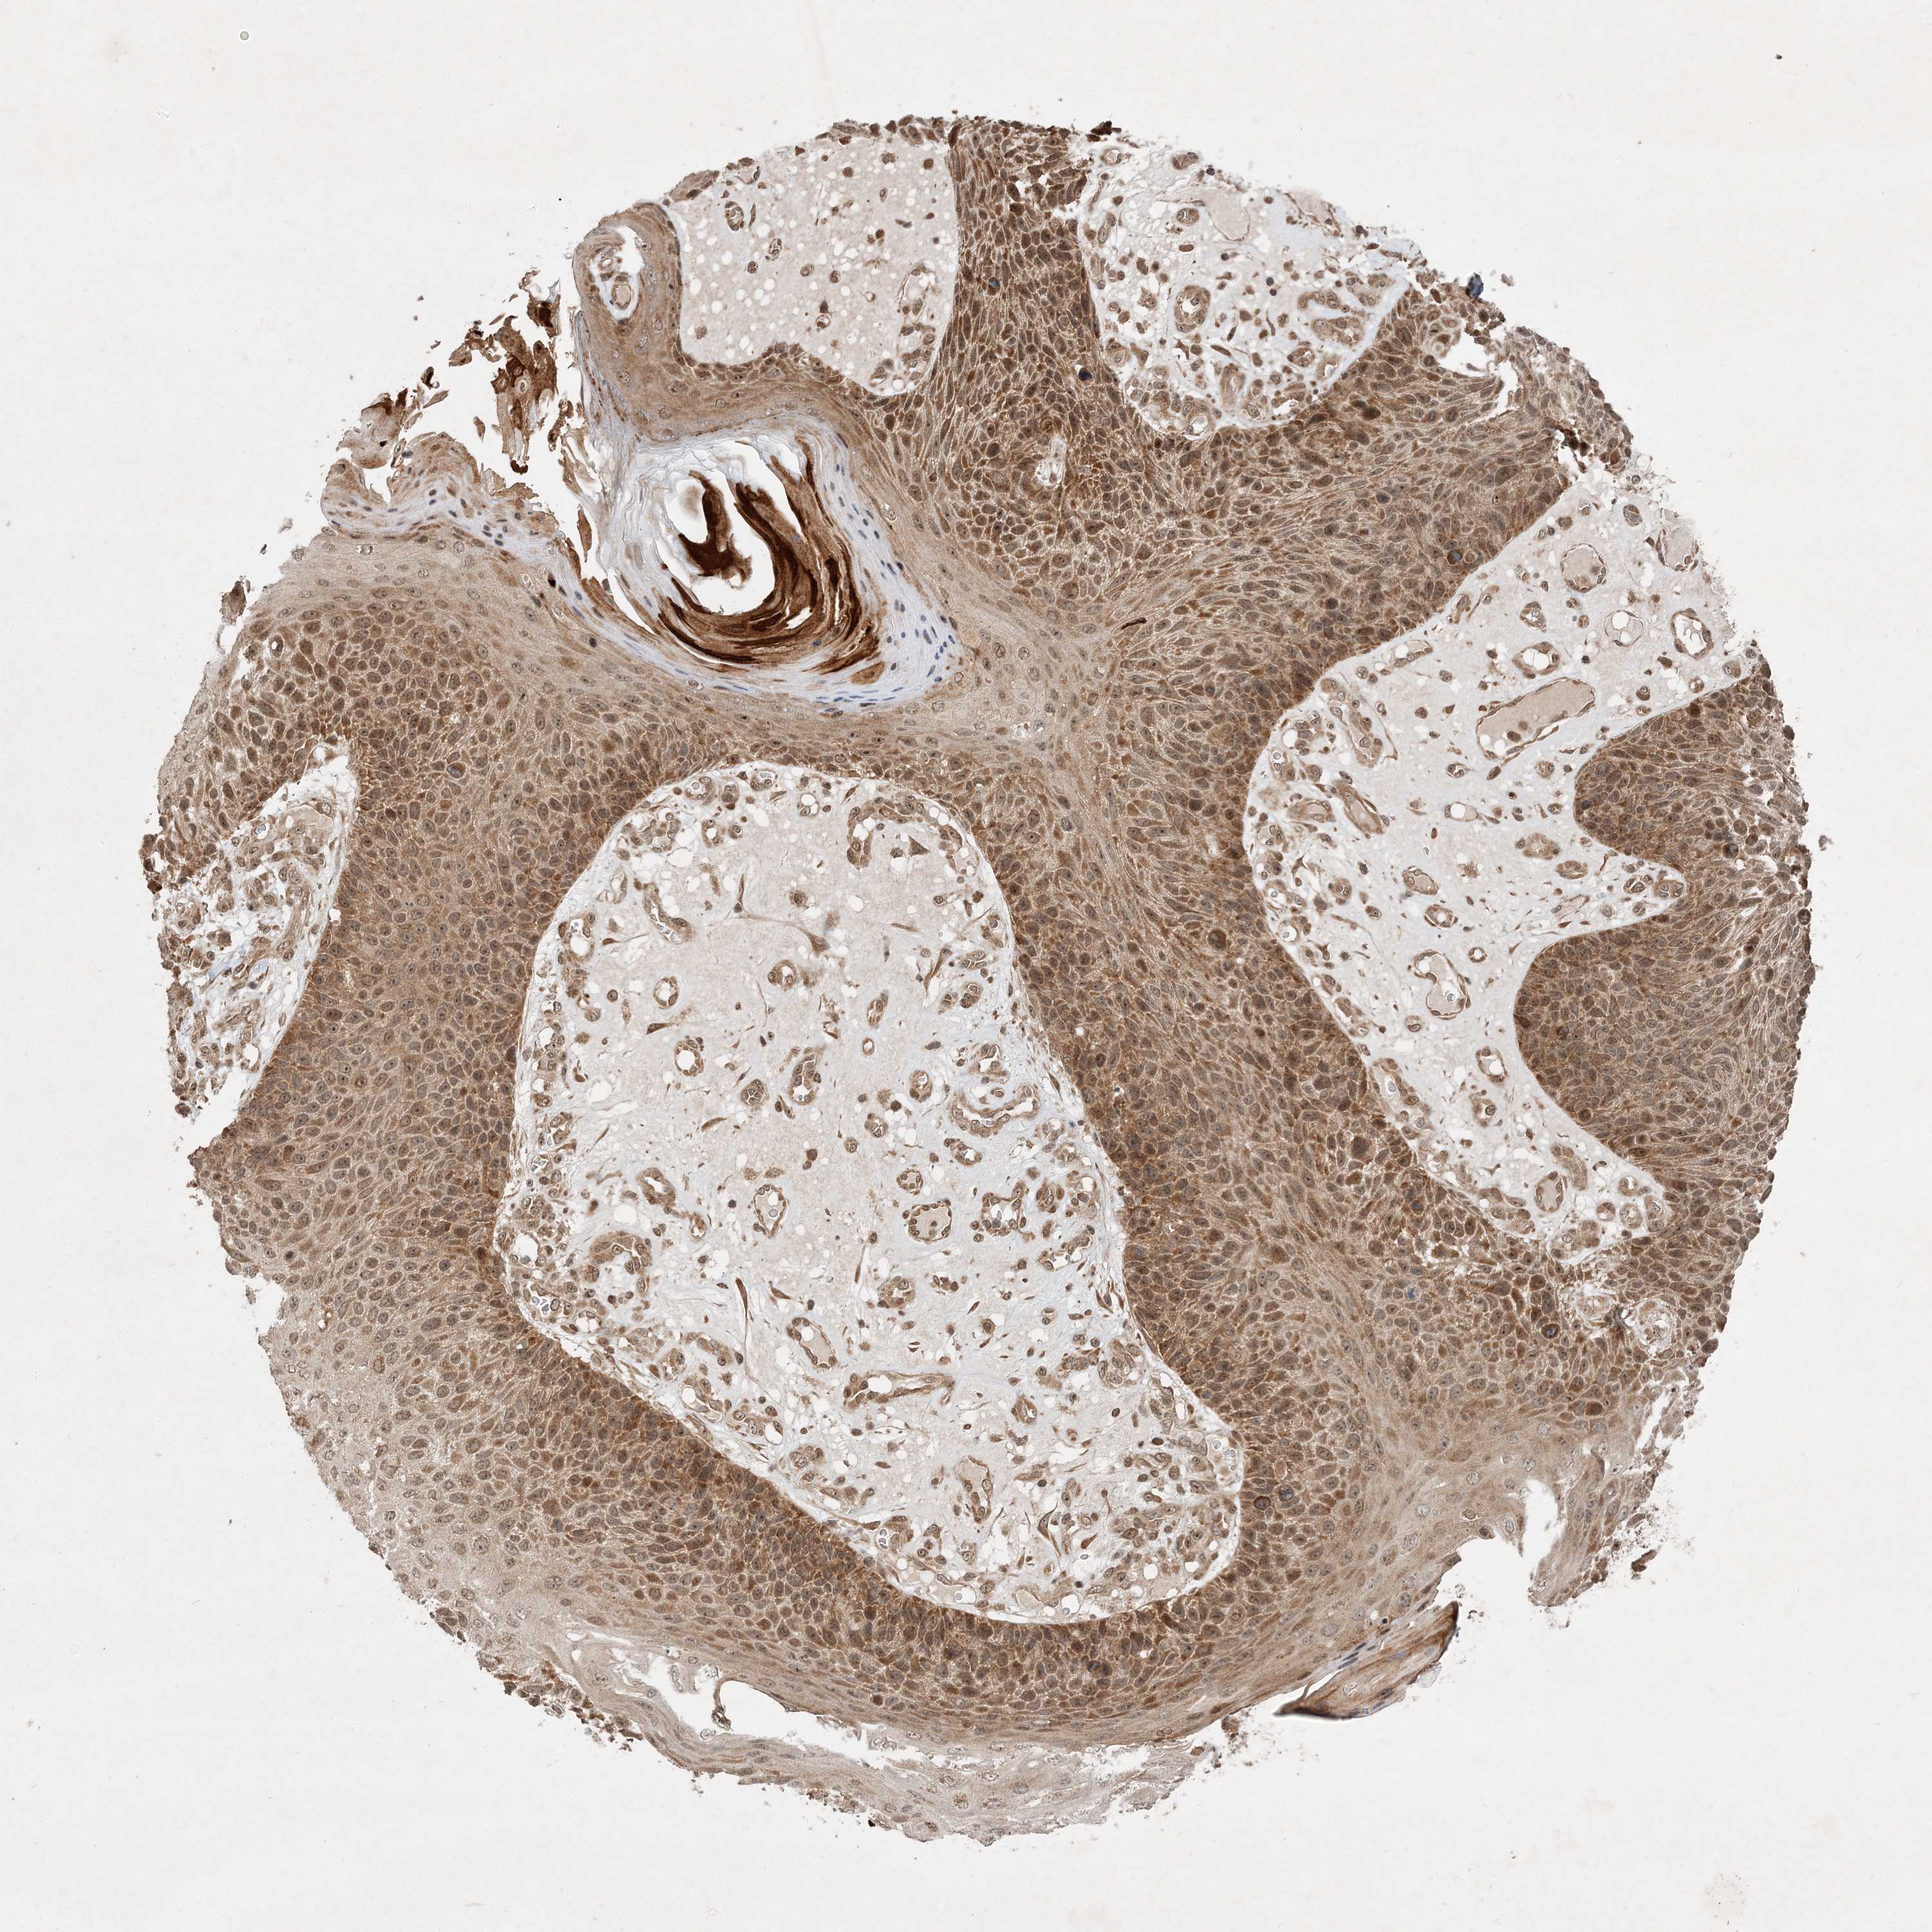

SKIN CANCER - Protein expressioni

A mouse-over function shows sample information and annotation data. Click on an image to view it in a full screen mode. Samples can be filtered based on level of antibody staining by selecting one or several of the following categories: high, medium, low and not detected. The assay and annotation is described here.

Antibody staining in the annotated cell types in the current human tissue is reported as not detected, low, medium, or high, based on conventional immunohistochemistry profiling in selected tissues. This score is based on the combination of the staining intensity and fraction of stained cells.

Each image is clickable and will lead to virtual microscopy that enables deeper exploration of all samples and also displays staining intensity scores, fraction scores and subcellular localization as well as patient and tissue information for each sample.

Antibody HPA035390

Basal cell carcinoma

Squamous cell carcinoma, NOS

Squamous cell carcinoma, metastatic, NOS